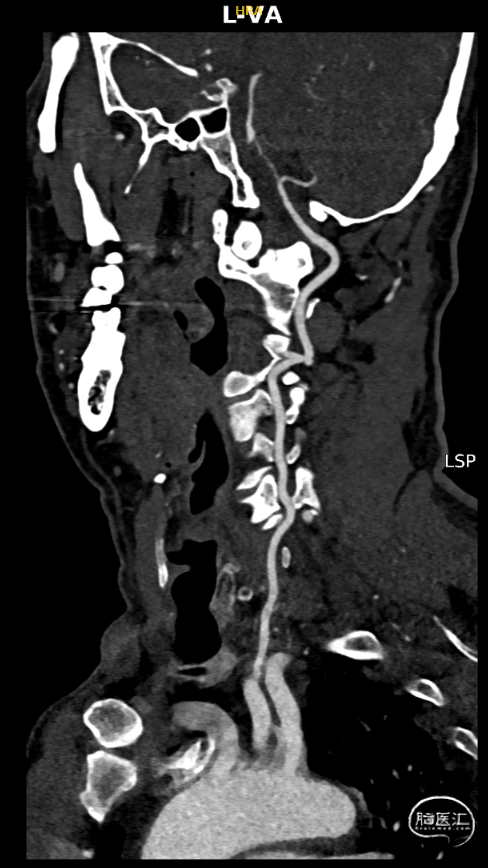

头颈联合CTA提示:左侧椎动脉V4段重度狭窄,右侧椎动脉V2以远闭塞。

右侧椎动脉闭塞、左侧椎动脉V4段重度狭窄。

左椎正侧位造影提示:LV4重度狭窄。

右椎正侧位造影提示:RV4以远闭塞,管腔内可见血栓形成。